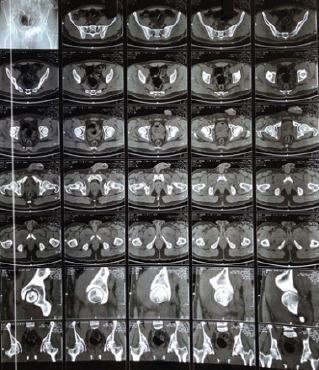

A 26-year-old man was brought to the emergency department following high-energy trauma due to a motor vehicular accident. He was in considerable pain with both hips in flexion, abduction, and external rotation. There was a restriction to the range of movement at bilateral hip joints. Clinical and radiological examination revealed bilateral anterior hip dislocation.

一名26岁男性因机动车事故遭受高能创伤后被送至急诊科。他双髋处于屈曲、外展和外旋位,疼痛剧烈。双侧髋关节活动范围受限。临床及影像学检查显示双侧髋关节前脱位。